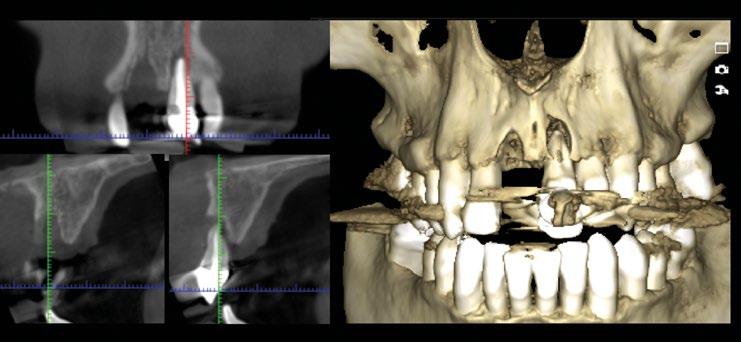

se aprecia una extensa reabsorción radicular interna, con el consiguiente defecto óseo, que se confirma con un CBCT (Fig. 3, 4, 5). Se informa a la paciente del riesgo de fractura espontanea. Esta solicita solucionar el problema antes de que avance más.

El plan de tratamiento propuesto es, previa planificación digital, la reposición postextracción del 21, relleno del gap bucal, injerto conectivo subepitelial y provisionalización inmediata. Tras 4 meses iniciar la fase de acondicionamiento final del tejido blando y a los 6 meses prótesis definitiva. Planificación digital de la posición ideal del implante y fabricación de la guía quirúrgica y corona provisional (Fig. 6 y 7).

Inserción totalmente guiada de un implante Prama (Fig. 10).

Se verifica la correcta posición y estabilidad del implante (Fig. 11 y 12).

En la exploración radiográfica en 3D (CBCT) se aprecia ausencia de cortical vestibular en 2.1 y un defecto óseo horizontal en 1.1 (Figura 3).

Una vez ajustada la oclusión eliminando por completo todos los contactos céntricos y excéntricos y explicando los cuidados postoperatorios tanto sistémicos como locales, se finaliza la cirugía. En el control radiográfico 2D y 3D se puede evidenciar la correcta colocación del material de regeneración y el ajuste de la prótesis provisional (Figura 11).